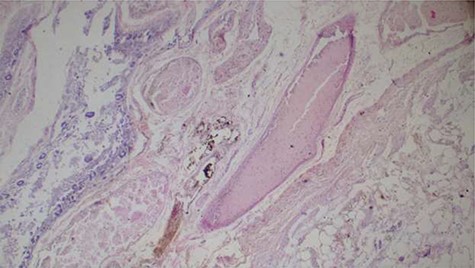

Histopathology analysis of the lung specimens revealed mixed chronic inflammatory infiltrates associated with pulmonary vascular thrombosis and areas of extensive necrosis (Figs 3 and 4). Bowel tissue sections revealed severe ischemic necrosis and mesenteric vessel thrombosis (Fig. 5). Thus, the primary causes of death were ruled to be ischemic colitis and pulmonary thrombosis due to COVID-19. The underlying disease conditions contributing to the cause of death being hypertensive heart disease, diabetes mellitus and septicemia.

Histopathology of the bowel tissue showing ischemic necrosis and the vascular thrombosis (hematoxylin and eosin ×100).